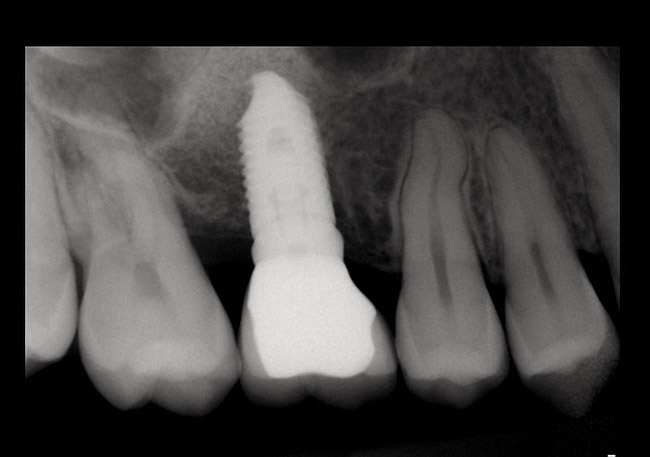

Fig 19. Peri-apical X-ray 13 months after sinus floor elevation and implant insertion.